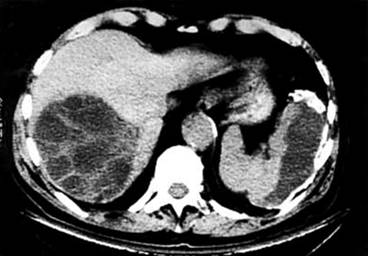

Người nhiễm loài ký sinh trùng E. granulosus dẫn đến sự phát triển một hoặc nhiều nang sán nằm chủ yếu ở gan và phổi, và thỉnh thoảng nằm trong xương, thận, lá lách, cơ, hệ thống thầnkinh trung ương và mắt. Giai đoạn ủ bệnh không xuất hiện các triệu chứng có thể kéo dài nhiều năm cho đến khi nang sán phát triển đến một mức độ mà gây ra các triệu chứng lâm sàng. Các dấu hiệu lâm sàng không điển hình gồm chán ăn, sụt cân và suy nhược. Các triệu chứng khác phụ thuộc vào vị trí các nang sán và áp lực tác dụng lên các mô xung quanh. Đau bụng, buồn nôn và nôn thường thấy khi các nang sán xảy ra trong gan. Nếu phổi bị ảnh hưởng, các dấu hiệu lâm sàng bao gồm ho mãn tính, đau ngực và khó thở.

Hình 5

Siêu âm là kỹ thuật hình ảnh được lựa chọn cho việc chẩn đoán cả hai hình thức đó là bệnh nang sán Echinococcosis và bệnh ở phế nang hay phổi. Kỹ thuật này thường được bổ sung hoặc xác nhận bởi chụp cắt lớp vi tính (CT-scanner) và/ hoặc chụp hình cộng hưởng từ (Magnetic Resonance Imaging_MRI). Đôi khi, các u nang có thể phát hiện tình cờ bởi chụp x-quang.